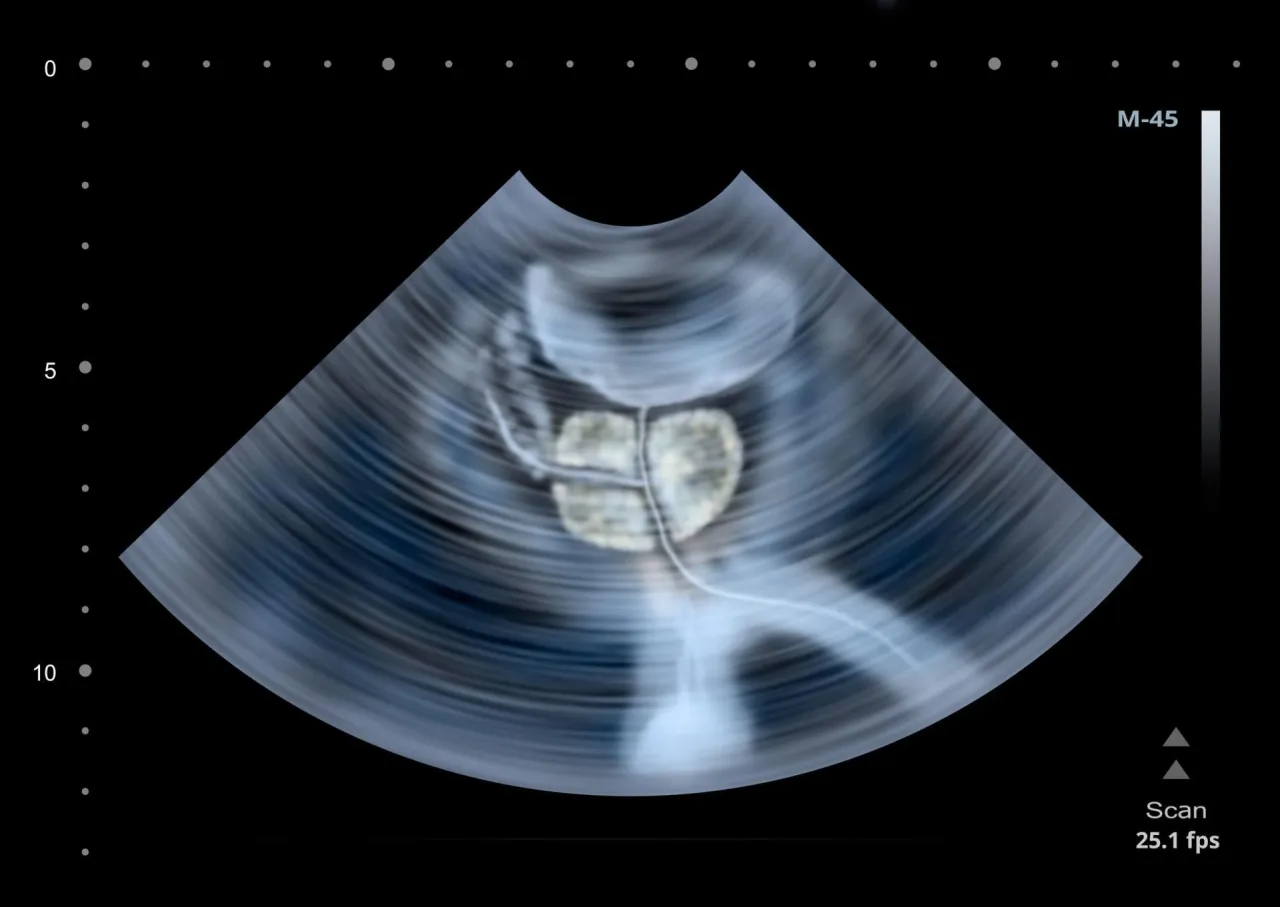

Kolejnym często zlecanym badaniem jest USG prostaty, zwłaszcza USG przezodbytnicze (TRUS Transrectal Ultrasound). Jest ono potrzebne, gdy urolog chce dokładniej zobrazować gruczoł krokowy. Podczas TRUS lekarz wprowadza do odbytnicy specjalną, cienką głowicę USG, która emituje fale ultradźwiękowe. Pozwala to na precyzyjną ocenę wielkości prostaty, jej struktury, a także wykrycie ewentualnych zmian ogniskowych, takich jak guzki. TRUS jest również niezwykle przydatne w przypadku konieczności wykonania biopsji prostaty, ponieważ umożliwia precyzyjne kierowanie igłą biopsyjną.